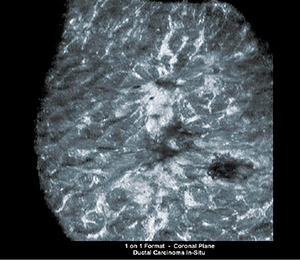

従来の超音波診断装置では描出が困難であった広範囲の冠状断面の描出も可能で(図2),位置関係を把握しやすく,乳頭から放射状に広がる乳管に沿った病変の診断に有用です。

図2 ABVSによる冠状断面の描出(非浸潤性乳管癌)